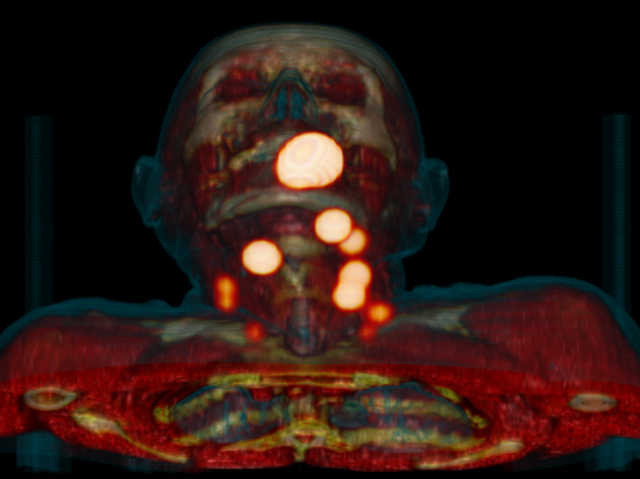

Tracking Tumours

Cancer rarely stays in the same place, which makes fighting it extremely tricky. Tumour cells can spread to other parts of the body via the lymph system - a complicated network of vessels and nodes. The patient pictured has head and neck cancer (largest yellow blob near mouth is a tumour). The smaller blobs are sentinel lymph nodes – the first nodes any cells from the tumour are likely to reach. The sentinel nodes have been identified using SPECT imaging, which works by tracking a radioactive substance through the lymph system. The tracer is injected near the tumour, and emits gamma rays, which are detected by a special camera. When the tracer drains into lymph nodes the bright hotspots result. These nodes must now be removed by a surgeon and tested for tumour cells, so doctors know what stage the cancer is at, and where to target treatment.